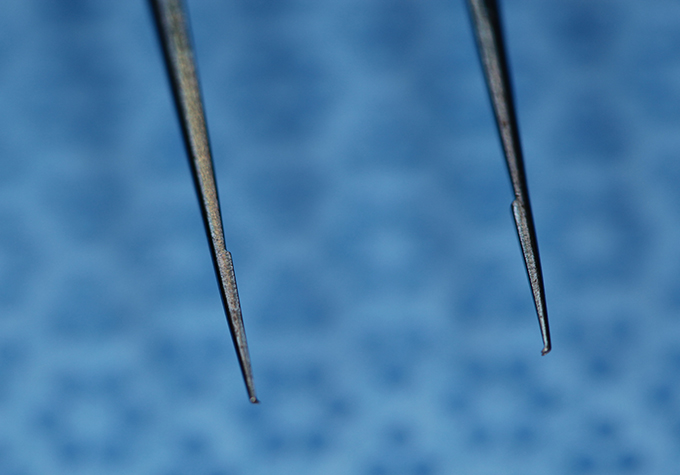

Bonn Forcep .12 Teeth - Enlarged

(aka Bonn Forceps)

catalog number: Storz E1809

Typical Use(s): Holding delicate tissue such as a scleral flap during glaucoma surgery; Has fine teeth smaller than classic .12 forceps